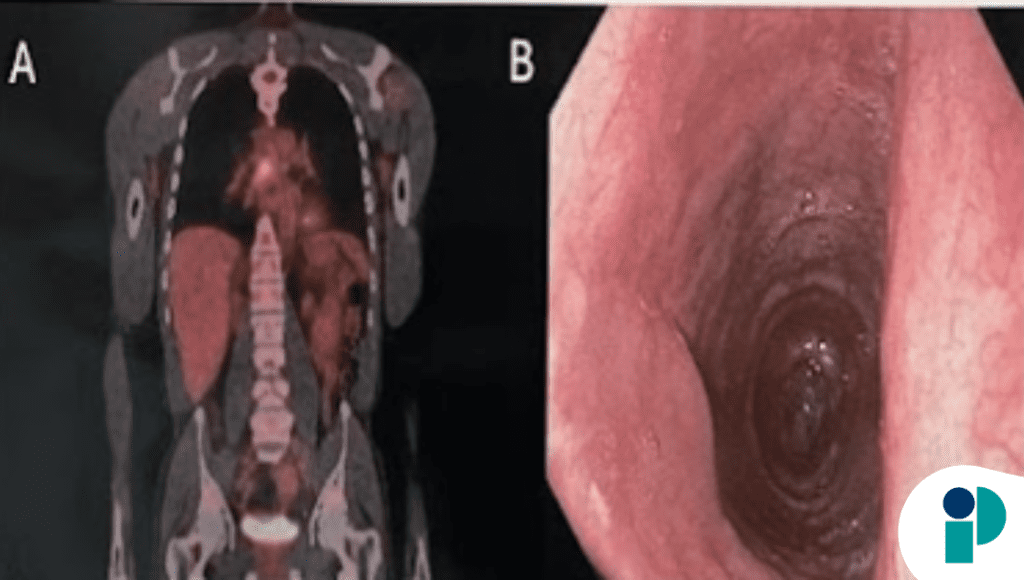

Durante la evaluación mediante endoscopia digestiva alta, se identificaron lesiones esofágicas sugestivas de compromiso infeccioso, lo que llevó a la toma de biopsias para confirmar la etiología. El estudio histopatológico evidenció infección fúngica esofágica, una causa poco frecuente pero clínicamente relevante de disfagia.

Aunque este tipo de infecciones suele asociarse a estados de inmunosupresión, también puede presentarse en contextos menos evidentes, lo que complica su reconocimiento temprano y retrasa el inicio del tratamiento adecuado.